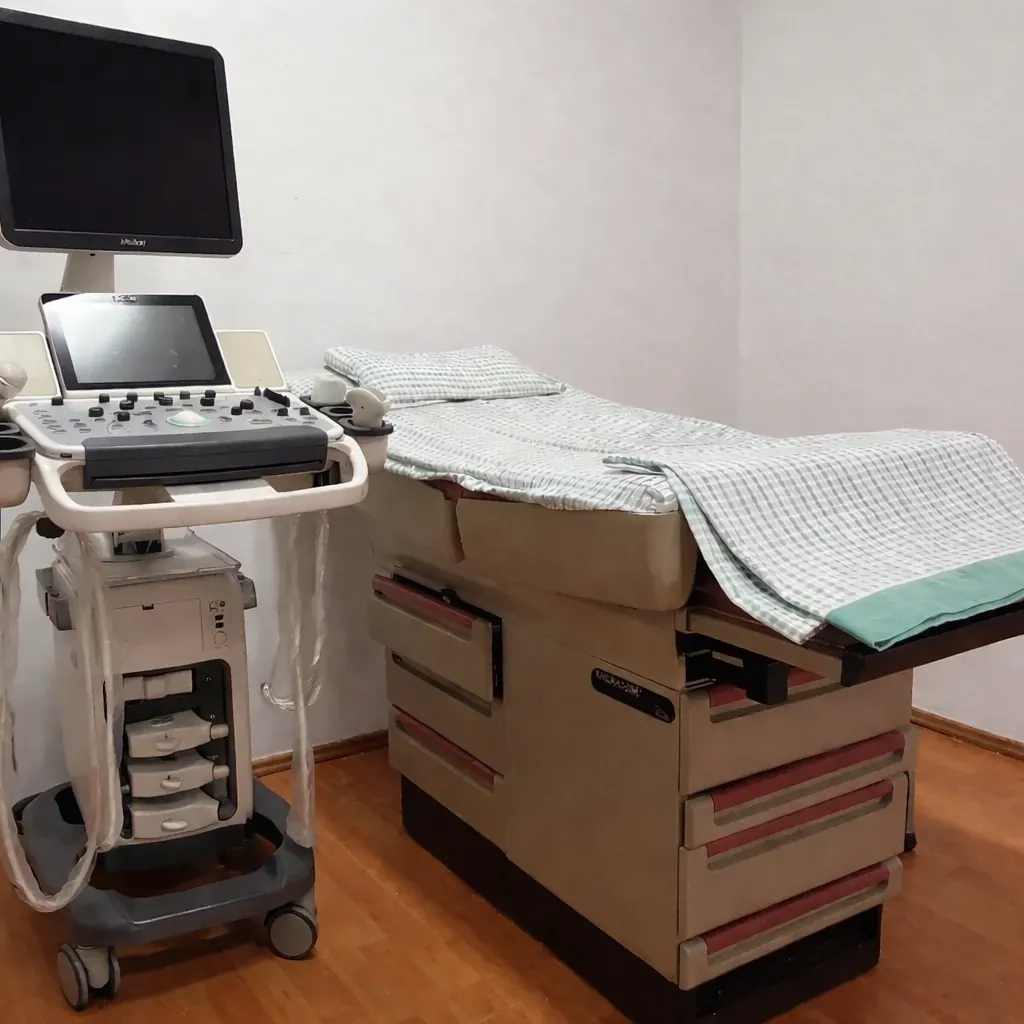

Para brindarte la mejor atención, nos cambiamos al Hospital Ángeles de Torreón, donde contamos con instalaciones de primer nivel y tecnología de vanguardia.

Ultrasonido 4D

Tecnología de última generación para visualizar el desarrollo y el bienestar de tu bebe.